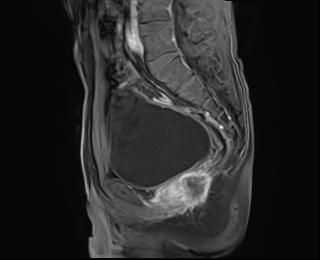

上圖為直腸癌術(shù)后復(fù)發(fā)患者。

MRI主要根據(jù)直腸壁的形態(tài)、厚度異常,腔內(nèi)軟組織塊影來診斷直腸癌,應(yīng)用直腸內(nèi)線圈、脂肪抑制脈沖序列進(jìn)行動(dòng)態(tài)增強(qiáng)檢查,獲取高分辨力的T1和T2加權(quán)像,可以清晰顯示直腸壁的各層結(jié)構(gòu),有助于確定腫瘤范圍、有無局部淋巴結(jié)轉(zhuǎn)移,以及顯示腹膜的種植轉(zhuǎn)移病灶。注意矢狀位圖像還可用于評(píng)估骶骨受累情況。參照直腸癌病理T分期,高分辨MRI的各期表現(xiàn)為:T1期表現(xiàn)為黏膜和黏膜下層的增厚,但固有肌層完整,T1加權(quán)成像增強(qiáng)呈不均勻強(qiáng)化,T2加權(quán)成像上腫瘤信號(hào)低于高信號(hào)的黏膜下層。T2期腫瘤組織進(jìn)入但未穿過固有肌層,肌層變薄但肌層與周圍脂肪交界面完好。T3期表現(xiàn)為腫瘤信號(hào)超出肌層,深入腸周脂肪,肌層與周圍脂肪的界面消失。T4期表現(xiàn)為腫瘤信號(hào)明顯侵入周圍鄰近組織器官。

直腸癌的MRI檢查還可鑒別腫瘤術(shù)后復(fù)發(fā)與瘢痕。復(fù)發(fā)腫瘤在T1加權(quán)像上常為低信號(hào),增強(qiáng)掃描呈中等強(qiáng)度,在T2加權(quán)象上為中等度高信號(hào);而纖維化或瘢痕呈低信號(hào)。有時(shí)二者鑒別困難,可以結(jié)合患者的臨床資料進(jìn)行綜合判斷,若患者的CEA值升高,出現(xiàn)骶骨前疼痛,臨床可考慮為腫瘤復(fù)發(fā)。